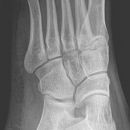

Fuß

Fuß a.p.

Komplexe anatomische Verhältnisse => Zusätzlich Schräg- und evtl. noch streng-seitliche Aufnahmen oder Vergleichsaufnahmen der Gegenseite anfertigen! Komplexe Luxationen/ Frakturen => großzügige CT-Indikation! Zentrale Kalkaneusfrakturen (vgl. Kalkaneus) => absolute CT-Indikation! Isolierte Frakturen des Os naviculare, der Ossa cuneiforma oder des Cuboids sind Raritäten => Immer nach zusätzlichen Verletzungen (Calcaneus, Talus, OSG,...) suchen!

Beurteilungskriterien

• Korrekte Stellung der Fußwurzelknochen zueinander? Kongruente Gelenkflächen? Gelenkspaltweiten zwischen den Fußwurzelknochen und Tarsometatarsalgelenken < 2,5mm? Interphalangealgelenke < 2mm? Luxation? Luxationen meist mit Frakturen (v.a. Talushals, Kalkaneus, OSG-Frakturen, Metatarsalbasen) kombiniert!

• "target areas" subtiler Frakturen: Talushals, Proc.ant.calcanei, Sustentaculum, Tuberositas ossis metatarsalis V!!!

• Typische Lokalisationen von Kapsel-Band-Ausrissen am Metatarsus:

• Os naviculare: dorsomedialer Sehnenausriss (Avulsion der Tuberositas, Ansatz M.tibialis post.)=> seitl. Aufnahme (DD Os supranaviculare)

• Os cuboideum: ventroplantarer, knöcherner Ausriss (M.tibialis post.)

• Tuberositas ossis metatarsalis V (M.peronaeus brevis) <=> DD Os peronaeum, Os Vesalianum

Cave:

• akzessorische Knochen (abgerundet mit zirkulärer Kortikalis, z.B. Os supranaviculare, Os supratalare, Os tibiale externum, Os Vesalianum, Os peroneum, Calcaneus secundarius, Os intercuneiforme) und Normvarianten der Apophsenentwicklung im Wachstumsalter, z.B. mehrkernige Tuberapophyse am Achillessehnenansatz, persistierender Apophysenkern der Basis ossis metatarsalis V.

• Ermüdungsfrakturen initial oft nicht erkennbar => Röntgenkontrolle in 8-10d.